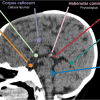

– Phổ biến, liên quan đến tuổi, hầu hết không có biểu hiện lâm sàng. * Hạch nền – Vôi hóa hạch nền thường tự phát với tần suất 0,3-1,5%, gia tăng theo tuổi. * Tuyến tùng – Tuyến tùng là một cơ quan nhỏ màu đỏ xám nằm trong chỗ lõm giữa các gò trên của trung não. Nó nằm dưới lồi thể chai, được ngăn với lồi thể chai bởi tấm mạch mạc của não thất III và các tĩnh mạch nằm trong tấm này. Tuyến tùng dài khoảng 8mm, nền của nó hướng ra trước bám vào thành não thất III. Tuyến tùng là một tuyến nội tiết có tầm quan trọng lớn về điều hòa. Nó làm thay đổi mức độ hoạt động của thùy trước tuyến yên, thùy sau tuyến yên, tuyến tụy nội tiết, tuyến cận giáp, vỏ thượng thận, tủy thượng thận và các tuyến sinh dục thông qua indoleamine và các hormone polypeptide. * Màng cứng – Vôi hóa thường gặp nhiều hơn cả ở lều tiểu não, mẫu vôi hóa dạng lá (laminar parttern) tần suất khoảng 2-20%. => Case lâm sàng 1: * Đám rối mạch mạc – Đám rối mạch mạc (Choroidal Plexus) nằm trong não bên thất chịu trách nhiệm sản xuất dịch não tủy. => Case lâm sàng 1: * Vôi hóa cương – Cương – habenula: ban đầu được dùng để chỉ cuống tuyến tùng nhưng dần dần nó được dùng để chỉ các nhóm tế bào (nhân cương) nằm ở bên dưới. Cương bao gồm một vùng lõm hình tam giác, gọi là tam giác cương, nằm ở mặt sau trong đồi thị tại đầu sau của vân tủy đồi thị. * Dây chằng đá yên – Những vôi hóa này liên quan tới thoái hóa, phụ thuộc tuổi tác, thường có dạng lá và nốt rải rác. – Di chứng chấn thương, phẫu thuật, thiếu máu và xạ trị, liên quan vùng nhuyễn não => Case lâm sàng 1: – Vôi hóa sau xạ trị – hóa trị * Hội chứng Sturge-Weber – Thuộc nhóm hội chứng thần kinh – da, ít phổ biến, xuất hiện lẻ tẻ, với tỷ lệ 1/50.000 ca sinh sống. * Xơ cứng củ – Bệnh xơ cứng củ (Tuberous Sclerosis – TS) là một bệnh lý thần kinh da đặc trưng bởi u mô thừa nhiều cơ quan. Có biểu hiện lâm sàng đa dạng, ưu thế tác động đến da, não, thận, tim, phổi, mắt và xương. Đột biến trội nhiễm sắc thể thường, dù đột biến tự phát lên tới 2/3 trường hợp. Liên quan với các bất thường NST 9 và 16. * U mỡ – Bệnh lý di dạng bẩm sinh lành tính, chủ yếu (80-90%) nằm ở đường giữa. Xuất phát từ những tế bào bất thường của khoang dưới nhện nguyên thủy (màng não nguyên thủy), thường là mô mỡ trưởng thành, không tân sinh. * Hội chứng Cockayne – Là bệnh lý di truyền lặn nhiễm sắc thể thường. * Hội chứng Gorlin-Goltz – Còn được gọi là hội chứng tế bào đáy Nevoid, bệnh lý di truyền trội nhiễm sắc thể thường. – Vôi hóa thành mạch: thường ở thành mạch máu lớn, liên quan xơ vữa mạch: động mạch cảnh trong, đốt sống, thân nền – Dị dạng mạch máu: => Case lâm sàng 1: => Case lâm sàng 2: => Case lâm sàng 3: + U mạch thể hang: thường vôi hóa dạng chấm ở thành mạch hoặc nhu mô não + Phình mạch: vôi hóa dạn đường, hình thoi, hình túi – HIV: vôi hóa tiểu não và chất trắng quanh não thất – Vôi hóa ở bệnh nhân Toxoplasmosis có thể mất sau điều trị – Sán não: giai đoạn vôi hóa, nốt vôi từ 1-2mm, không có phù não xung quanh. Các nốt vôi hóa nhỏ, thường ở ranh giới chất trắng và chất xám. => Case lâm sàng 1: – U thần kinh đệm ít nhánh (Oligodendroglioma) => Case lâm sàng 1: – U sọ hầu (Craniopharyngioma) – U vùng tuyến tùng (Pineal region tumors) / U tế bào mầm (Germ cell neoplasm) – U tế bào thần kinh trung ương (Neurocytoma) – U màng não thất (Ependymoma) – U thần kinh đệm hạch (Ganglioma) – U nguyên tủy bào (Meduloblastoma) – U sao bào lông (Pilocytic astrocytoma) – Rối loạn chuyển hóa ảnh hưởng đến cân bằng Calci, chủ yếu liên quan đến hạch nền => Case lâm sàng 1: => Case lâm sàng 2: => Case lâm sàng 3: – Vôi hóa đối xứng, không có hiện tượng phù não và không có hiệu ứng choán chổ – Chuỗi xung nhạy cảm từ (Susceptibility weighted imaging – SWI) là một chuỗi xung Gradient echo khai thác sự khác nhau về hiện tượng nhạy cảm từ của các chất như máu, kim loại, can-xi… Bên cạnh thông tin về cường độ tín hiệu (magnitude), chuỗi xung SWI còn ghi nhận những thông tin về thay đổi pha trong mỗi voxel. Trên hình ảnh SWI, cả can-xi và các sản phẩm của xuất huyết đều giảm tín hiệu. Để phân biệt hai nhóm này cần có hình ảnh phase. Trên hình ảnh phase hai nhóm này sẽ có tín hiệu ngược nhau. – Các tĩnh mạch vỏ não hoặc xoang tĩnh mạch màng cứng thường được dùng để đối chiếu trên hình ảnh phase. Xuất huyết có phase shift tương tự các tĩnh mạch. Ví dụ nếu các tĩnh mạch có màu đen trên hình ảnh phase thì các sản phẩm xuất huyết cũng có màu đen trên hình ảnh phase, còn can-xi sẽ có màu trắng. Ngược lại nếu các tĩnh mạch có màu trắng trên hình ảnh phase thì các sản phẩm xuất huyết cũng có màu trắng trên hình ảnh phase, còn can-xi sẽ có màu đen. + Tín hiệu vôi: tăng trên Phase => Case lâm sàng 1: => “Left handed system” – Hãng Siemens + Canon: => Case lâm sàng 1: + Tín hiệu vôi: giảm trên Phase => Case lâm sàng 1:II. Chẩn đoán hình ảnh

– Habenula có vai trò trong đau, hành vi sinh sản, dinh dưỡng, chu kì sinh học, đáp ứng với căng thẳng và học tập.

– Vôi hóa habenula có dạng đường cong nằm ở phía trước tuyến tùng. Trong y văn, người ta có nhận thấy mối liên quan giữa vôi hóa habenula và rối loạn chức năng habenula, tâm thần phân liệt và khả năng học tập.

– Vôi hóa thường sau 2 tuổi và chiếm khoảng 10%.2. Vôi hóa loạn dưỡng